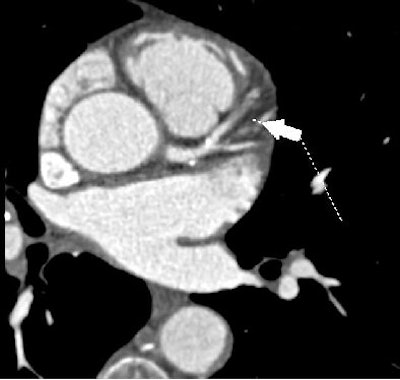

| All images were acquired in a 62-year-old man presenting to the hospital for evaluation of chest pain. Left heart catheterization confirms occlusion of the mid-LAD. |